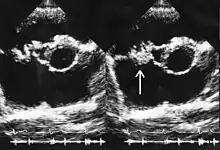

Side-by-side echocardiogram cross-sections of a human heart. In the second image a white arrow points at a mass on the tricuspid valve.

This echocardiogram shows vegetations on the tricuspid valve (white arrow) caused by infective endocarditis. The patient received conventional treatment, with ampicillin, imipenem, and glucocorticoids, and recovered fully after heart surgery.[29]

It is traditionally believed that so-called "deep" infections—such as osteomyelitis or infective endocarditis—should be treated with bactericidal antibiotics, not bacteriostatic ones. Nevertheless, preclinical studies were conducted to assess the efficacy of linezolid for these infections,[30] and the drug has been used successfully to treat them in clinical practice. Linezolid appears to be a reasonable therapeutic option for infective endocarditis caused by multi-resistant Gram-positive bacteria, despite a lack of high-quality evidence to support this use.[31][32] Results in the treatment of enterococcal endocarditis have varied, with some cases treated successfully and others not responding to therapy.[33][34][35][36][37][38] Low- to medium-quality evidence is also mounting for its use in bone and joint infections, including chronic osteomyelitis, although adverse effects are a significant concern when long-term use is necessary.[39][40][41][42][43][44]